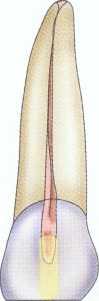

Given the goals and constraints of endodontic access, a distinctive shape is required for each tooth type based on the most common anatomic features of the crown as well as the radicular morphology. Maxillary central and lateral incisors share common coronal and radicular anatomy,5,6 as do the maxillary premolar and molar tooth groups. The same can be said for the mandibular teeth. Although maxillary and mandibular canine teeth share common coronal and radicular form, the lack of two canals in the maxillary canine as well as less frequent lingual inclination result in a somewhat more constrained access form in the maxillary canine.

Maxillary Incisors

In uncomplicated cases, both maxillary central and lateral incisors share a common triangular-shaped access from the lingual surface of the tooth. The classic access design places the access centrally on the lingual surface between the incisal edge and the cervical edge7 ( Figure 2-14). This design is reflective of the poor restorative choices available in the past as well as the limited options for "hiding" the access more cervically. Such a design results in a much larger amount of dentin removal at the lingual cervical edge to gain straight-line access. With improved esthetic bonded composites, the classic access form can be modified by placing it considerably more incisally (Figure 2-15). The initial penetration should be approximately in the middle of the lingual surface of the tooth, not just above the cingulum as has been previously described.' After locating the canal, the clinician uses a long, tapered diamond to extend the access even further incisally and laterally. An additional modification for use with rotary instrumentation is to slightly notch the middle of the incisal extent of the access (see Figure 2-15). This allows even better straightline access and greatly decreases the potentially catastrophic cervical flexure of the rotary instruments that can contribute to premature, unexplained fracture.